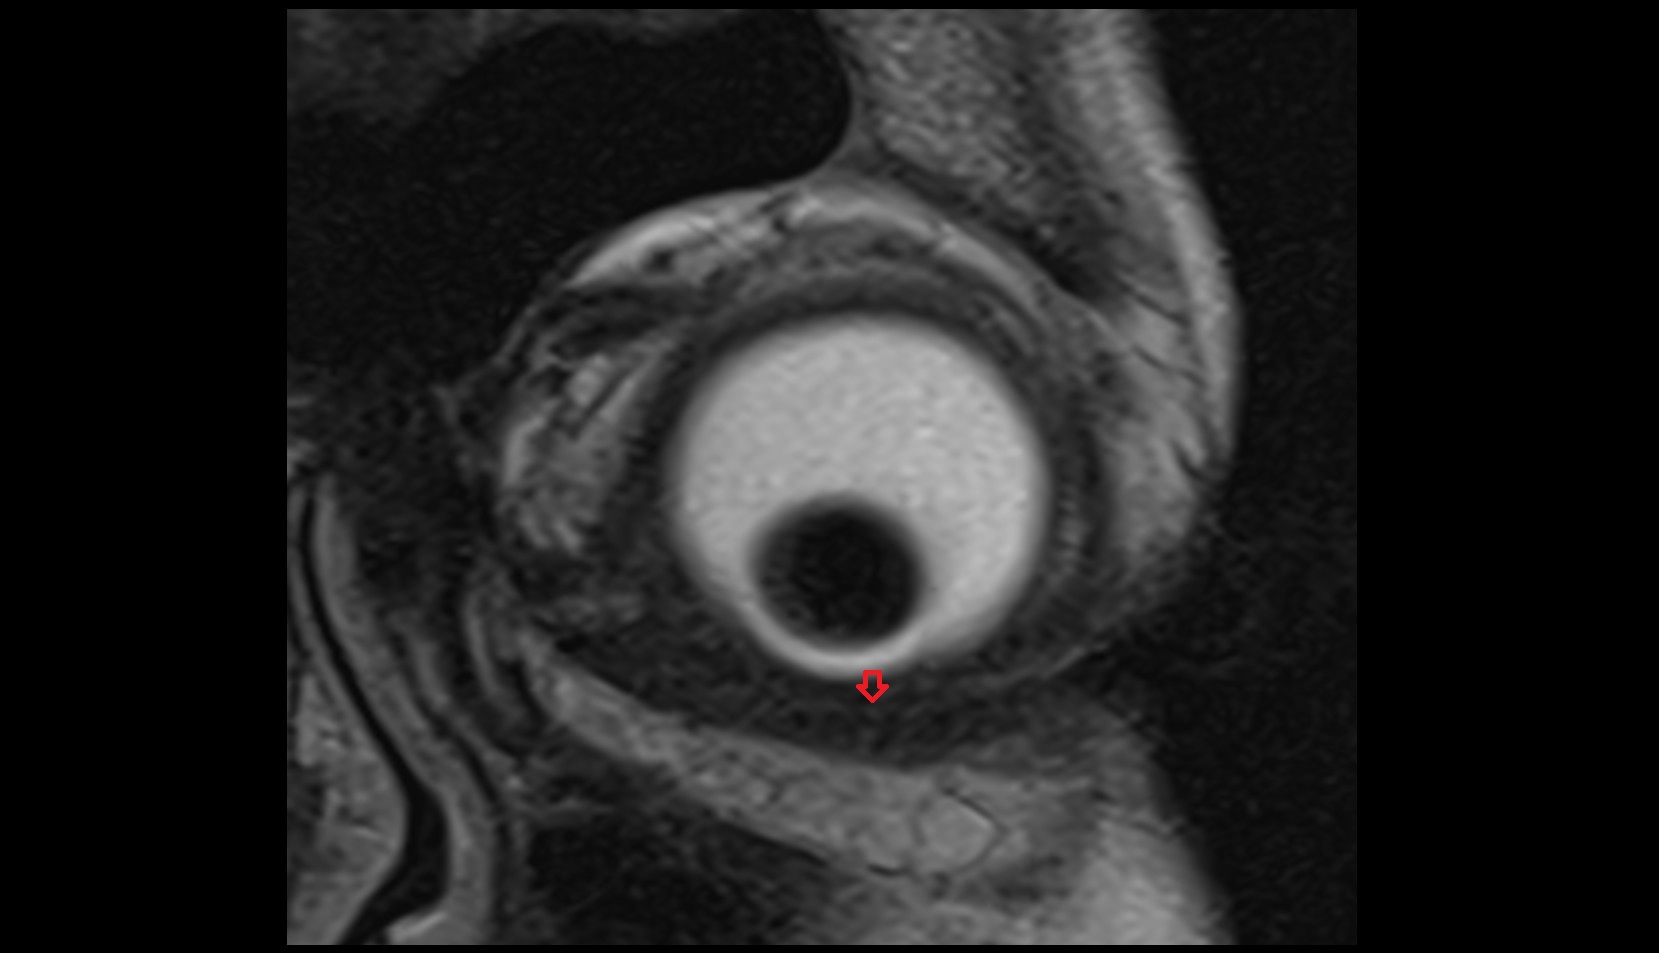

- Peripheral zone of prostate

- Anterior Fibromuscular Stroma of prostate

- Central zone of prostate

- Transitional zone of prostate